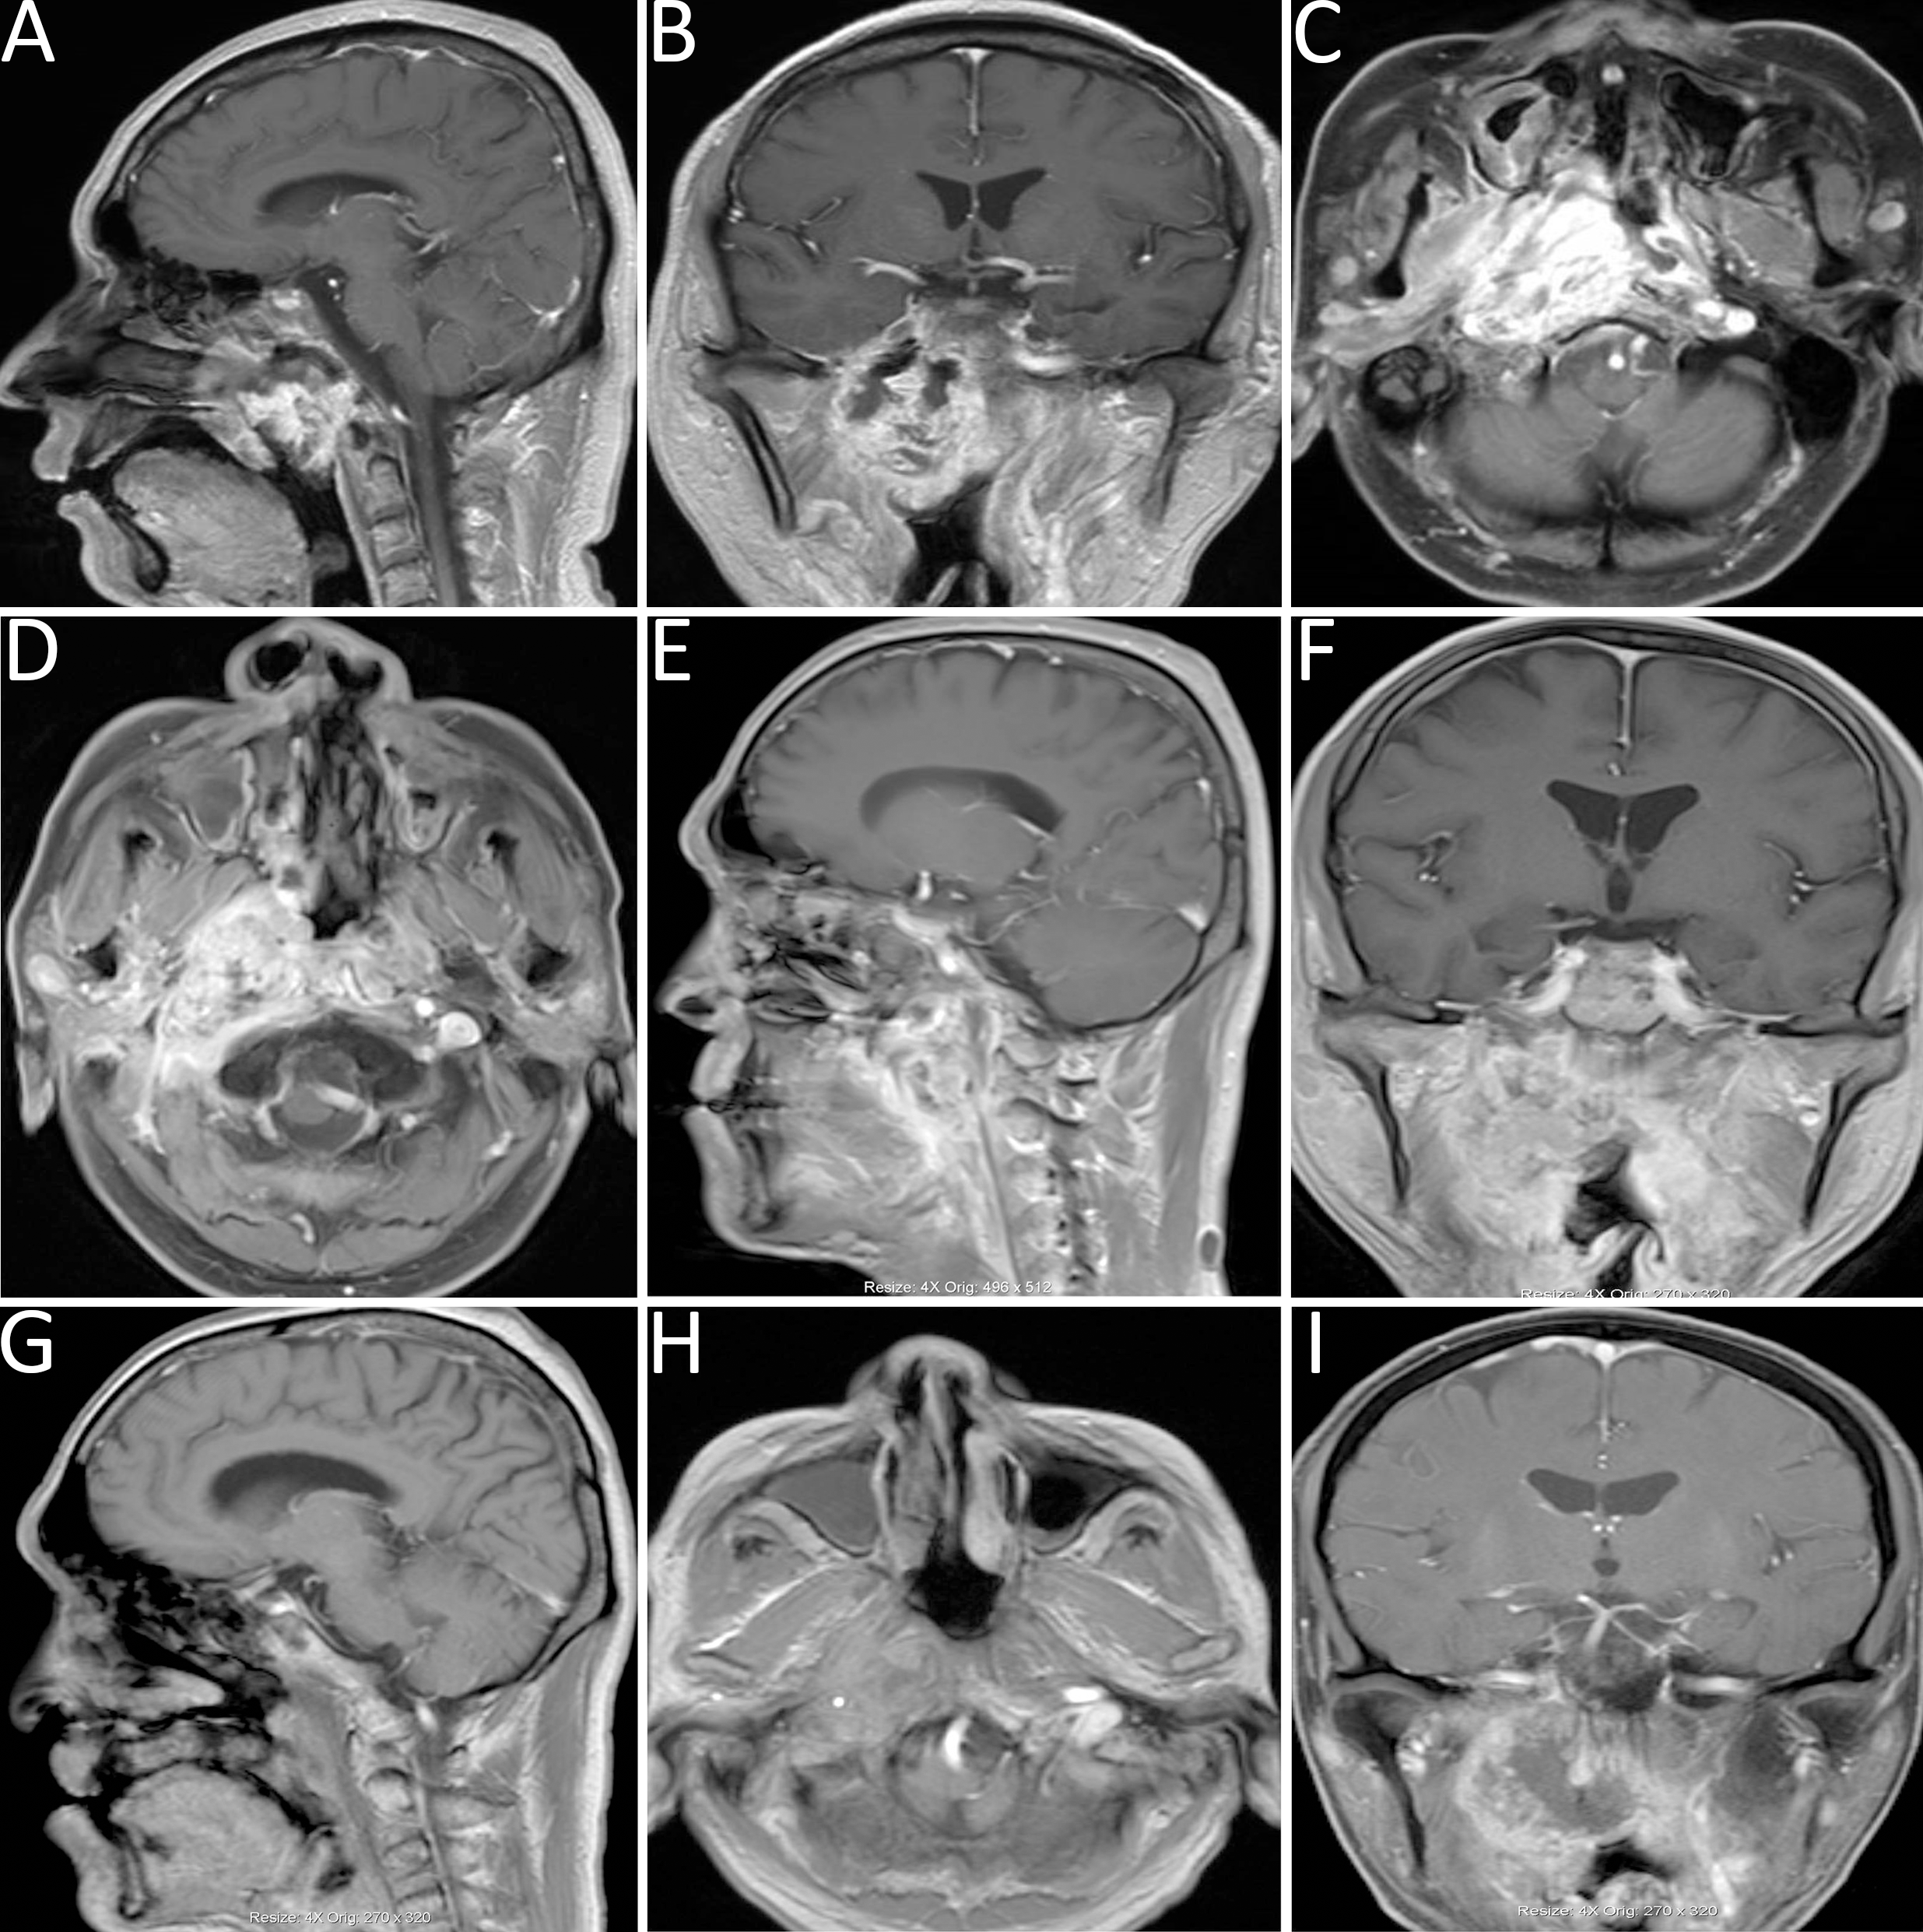

Nasal endoscopic examination revealed a nasopharyngeal mass with extensive necrotic tissue and pronounced pulsation. MRI of the head demonstrated abnormal signal intensity involving the nasopharyngeal roof and right parapharyngeal space, with areas of uneven contrast enhancement, as well as linear enhancement at the margin of the left nasopharyngeal wall (refer to Figures 2A–C). Given the clinical presentation and imaging findings, recurrent nasopharyngeal carcinoma accompanied by nasal bleeding was suspected.

Figure 2

(A-C) Head MRI demonstrated abnormal signal intensities in the nasopharyngeal roof and right parapharyngeal space, with heterogeneous contrast enhancement and linear enhancement at the margin of the left nasopharyngeal wall. (D-F) MRI revealed a space-occupying lesion in the right parapharyngeal space. (G-I) Follow-up MRI indicated marked liquefaction and necrosis within the surgical cavity, reduction of the primary lesion, and findings consistent with a partial response (PR).

Case 2: A 49-year-old male with a history of right-sided hearing loss for one year and headaches for four months, following a five-year history of nasopharyngeal carcinoma underwent re-evaluation at this institution. Contrast-enhanced MRI indicated a space-occupying lesion in the right parapharyngeal space, consistent with recurrent nasopharyngeal carcinoma (refer to Figures 2D–F).

Follow-up MRI demonstrated significant liquefaction and necrosis within the lesion cavity, along with a reduction in the size of the primary tumor, findings indicative of a PR (refer to Figures 2G–I).